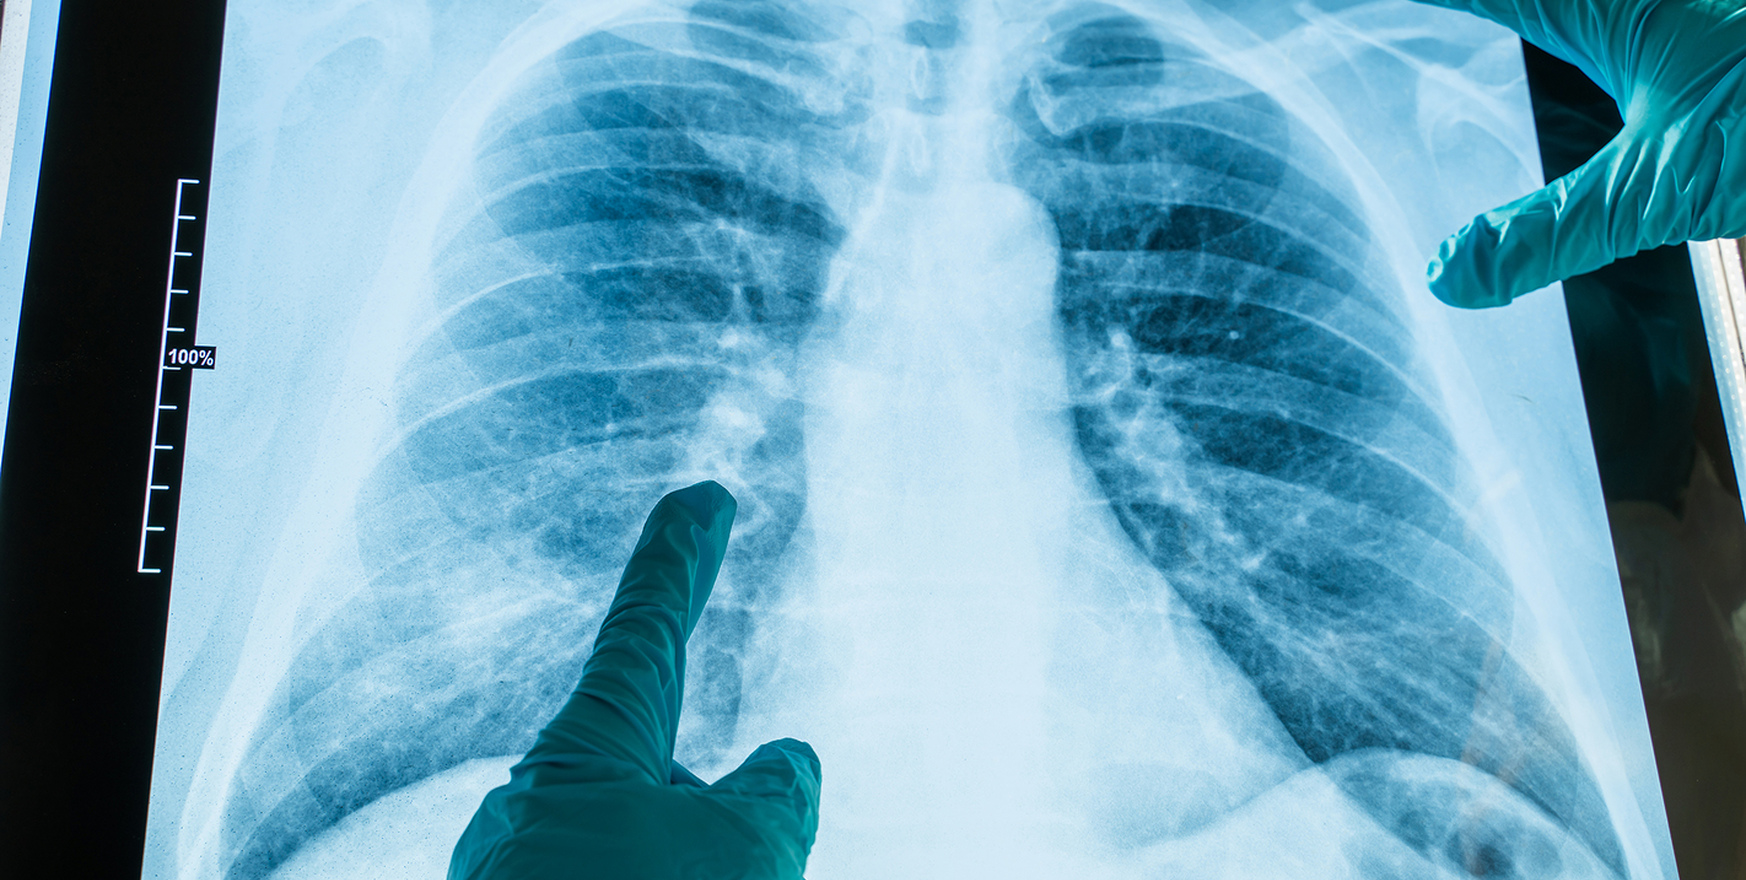

- При выявлении изменений на флюорографии или рентгене лёгких.

- Диагностика и консультация фтизиатра – проводится анализ мокроты, кожная проба Манту, Диаскинтест, рентген или КТ грудной клетки.

- При подозрительных изменениях на рентгене или после контакта с больным туберкулёзом.